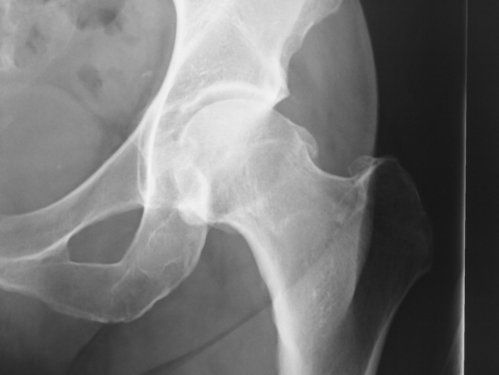

Displasia de cadera

DISPLASIA DE CADERA EN EL ADULTO

La displasia de cadera del adulto (DCA) es una entidad clínica que es el resultado de la anomalía en el desarrollo del techo del acetábulo o de las secuelas de un tratamiento fallido para corregirlo.

Todos hemos conocido algún caso de un recién nacido que el pediatra explica a la familia que las caderas “se le salen de sitio” y que hay que aplicar varios pañales o incluso un arnés para que las piernas se queden abiertas y así las cabezas del fémur permanezcan dentro del acetábulo en los primeros meses. Sí la cabeza del fémur no queda completamente cubierta por el acetábulo, tiende a escaparse hacia fuera.

Esta situación hace que la cadera se desgaste más rápidamente de lo que se considera normal con la edad.